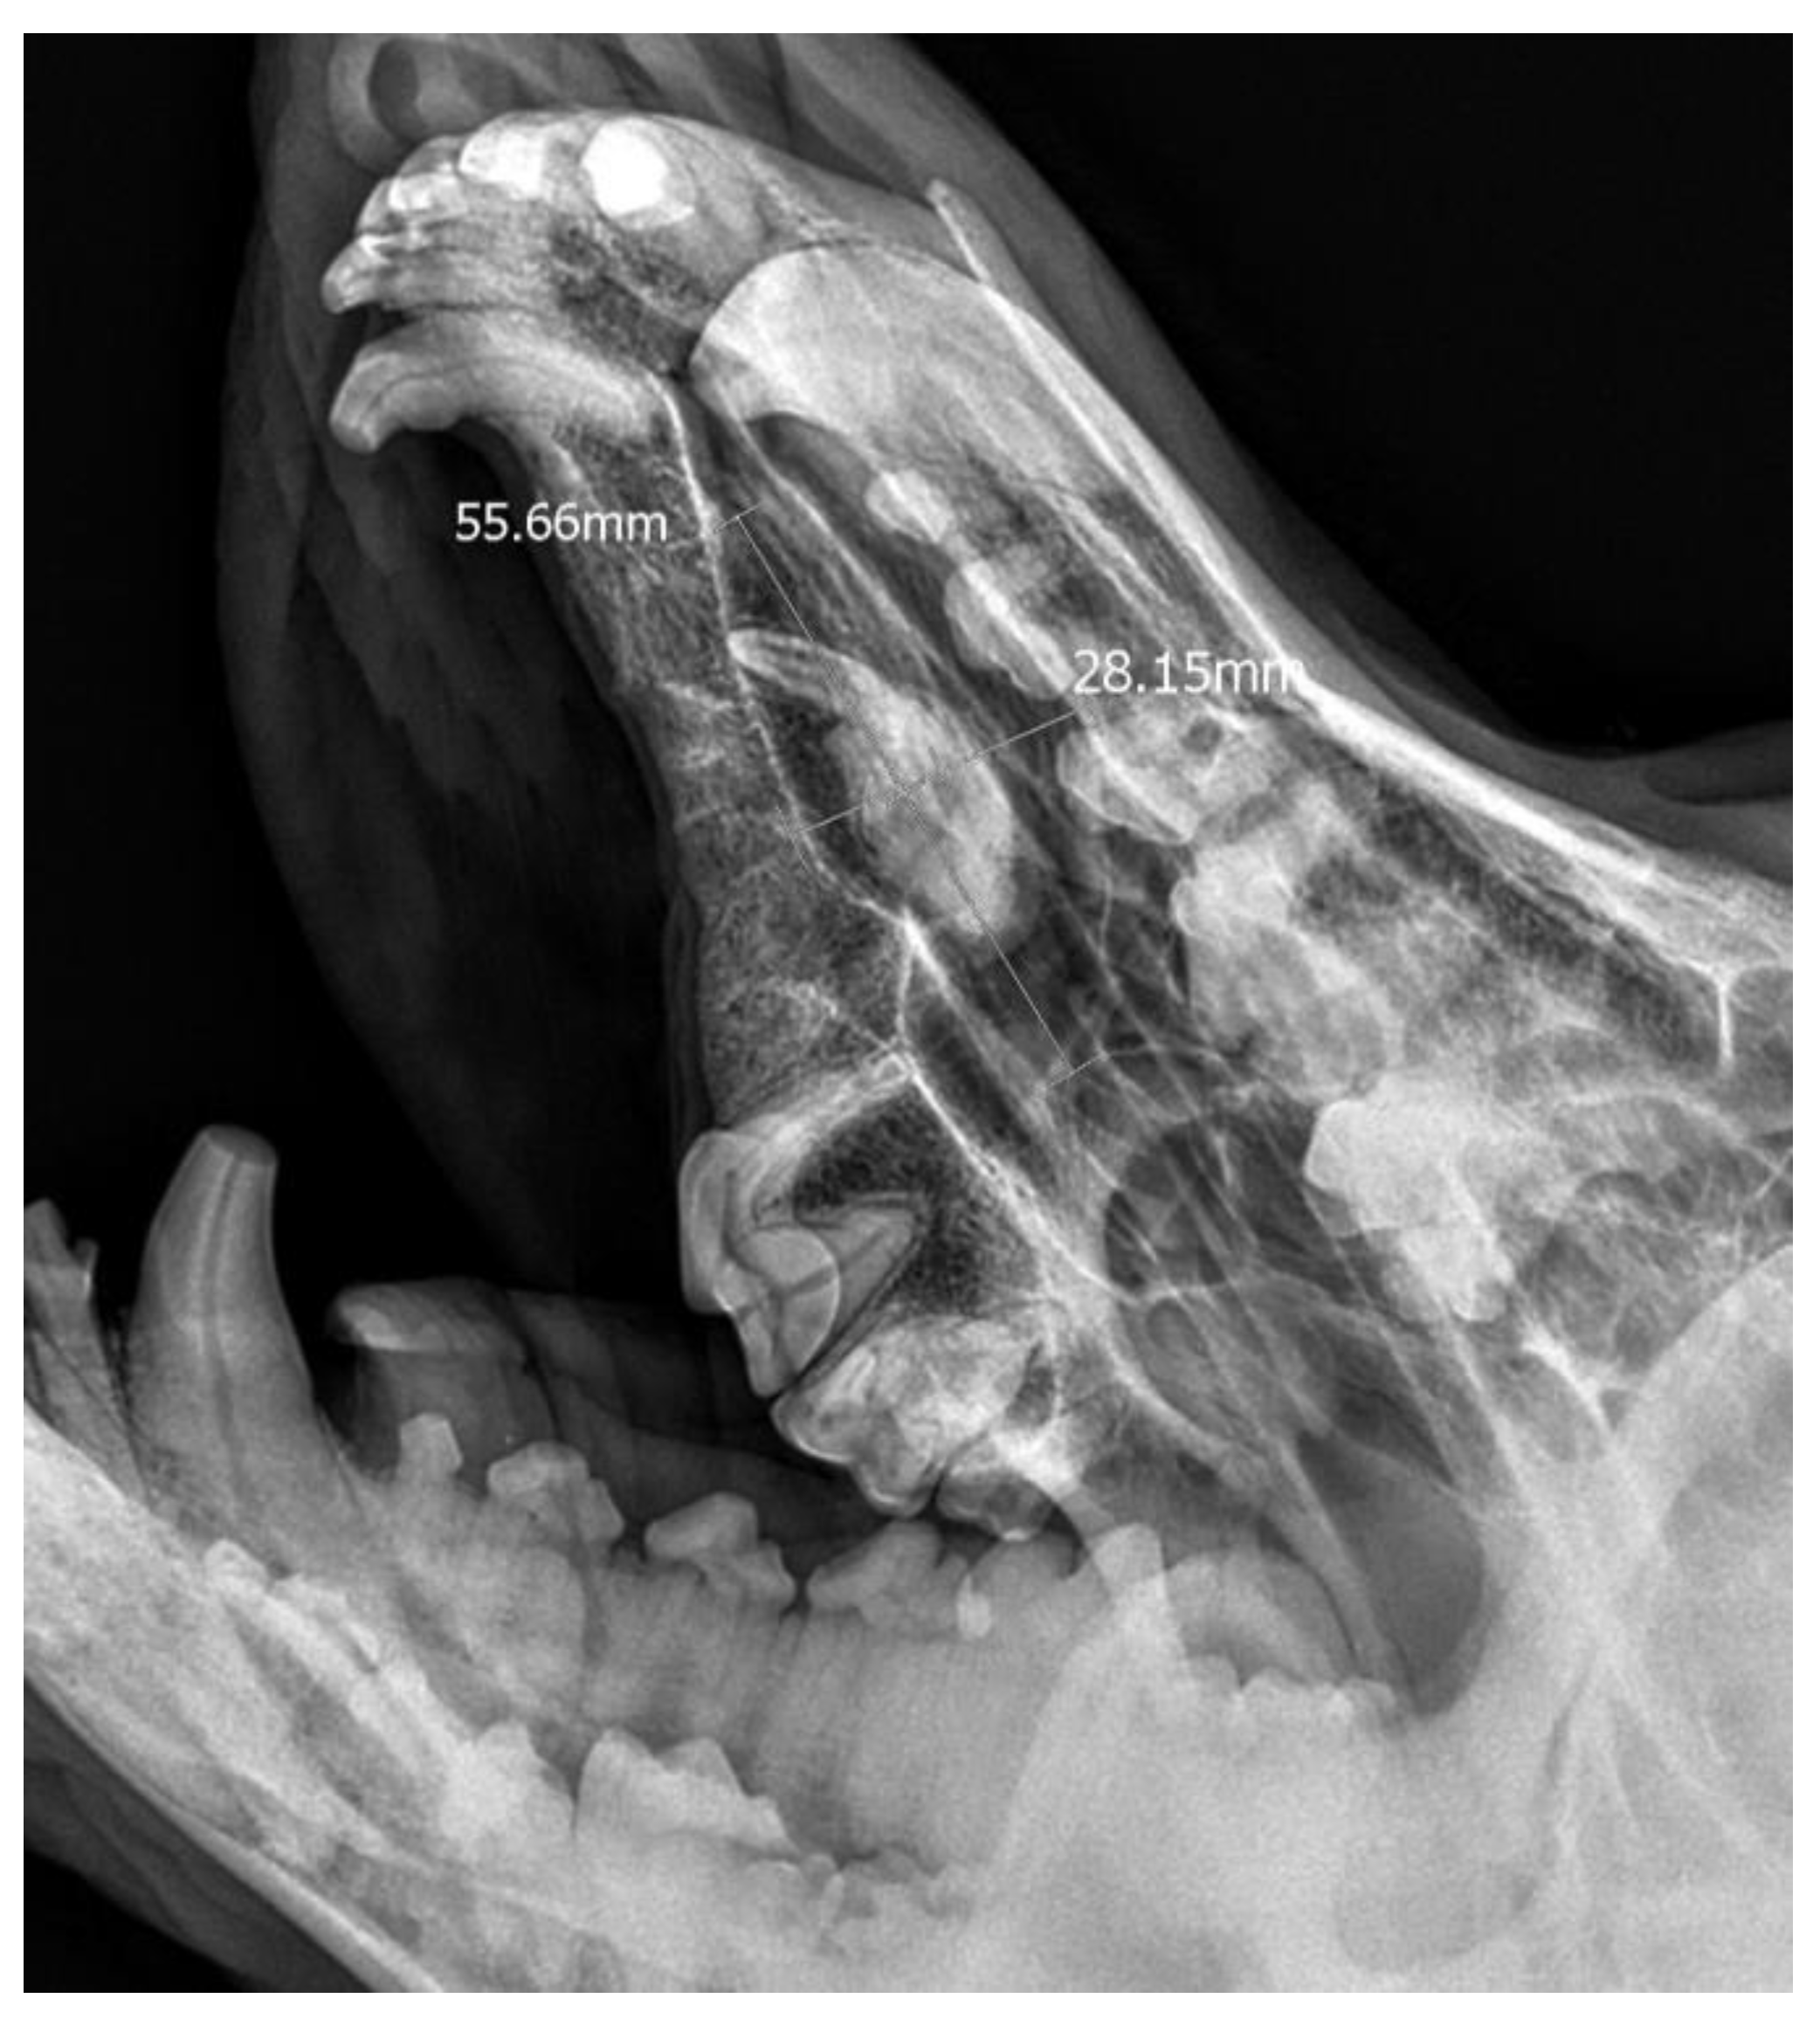

A 3-year-old German Shepherd dog was referred with a suspected periapical abscess of a tooth on the right side. The medical history of the pet client reported that the dog had been treated for chronic rhinitis for 6 months. On clinical examination, tooth 104 (right maxillary fang) was observed to be missing, with no wounds or fistulas in the oral cavity. Rhinoscopic examination showed features of chronic rhinosinusitis, with convexity of the nasal wall mucosa on the right side of the nasal cavity, without proliferative changes or foreign bodies. Radiological examination revealed the presence of an ectopic tooth located outside the alveolar process in the region of the maxillary cranium. Its shape was not characteristic of any normal tooth. It had a soppy crown and an incompletely formed root. The tooth was surrounded by a dentigerous cyst measuring 5.6 × 2.8 cm (Figure 5). After tooth extraction using the CLP technique and cyst lysing, the bone defect was filled with a hydroxyapatite polymer material previously soaked in 0.9% NaCl. The plasticity of the material was exploited so that it was possible to fill the bone defect with the material through a dissected bone window of 3 cm in diameter without enlarging the bone defect. A follow-up X-ray 28 days after the procedure showed normal filling of the defect with bone, without signs of inflammation or granulation formation within the jawbone. On clinical examination, resolution of nasal discharge problems and the absence of features of inflammation within the nasal cavity were observed (Figure 6).

Figure 5. X-ray in oblique head projection. The image shows an ectopic tooth along with an alveolar cyst (the dimensions of the cyst are marked).